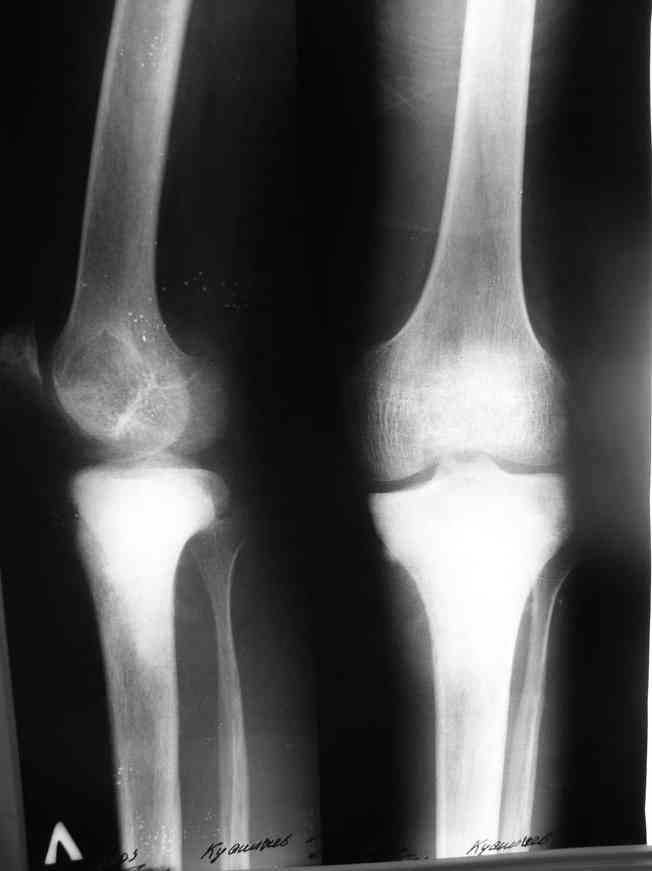

важаемые коллеги! Поступил больной 22 лет. Болен с января 2006 - появились боли в области верхнейтрети голени. При первичном осмотре в поликлинике был заподозрен первично-хронический остеомиелит - осмотрен гнойным хирургом - произведена биосия . Заключение - хондросаркома. Осмотрен онкологом - с учетом характера опухоли - химиотерапия, лучевое лечение не показано. Предложена либо ампутация, либо решение вопроса о возможности выполнения органосохраняющей операции. При обращении к нам произведена сцинтиграфия скелета - зоны гиперфиксации РФП: верхняя треть голени- 960%, нижняя треть бедра - 380%, Дистальный метафиз голени и затылочная область - 140%. В легких - метастазов нет. Произведена КТ (картинки в приложении). Учитывая абсолютную нестыковку рентгенологических и морфологических данных повторно биопсия. Выявлено, что первичная биопсия выполнялась из поверхностной параоссальной зоны - там локализованы хрящеподобные массы, далее очень плотная кость без хрящевых участков - биоптат взят фрезой с большим трудом. Морфологического заключения пока нет. Хотелось бы узнать Ваши варианты диагноза и соответственно тактику.

Не специалист по онко ортопедии, но по локализации (бедро, большеберцовая и плечевая кость), возрасть, в данный момент отсутствия метастаза и формация новой кости с мягкотканним вовлеченим, процесс больше напоминает остеосаркому большеберцовой кости.

Припухлость над опухолью и кожные изменения, подобно воспалительной и боли при нагрузке могут быть приняты общими ортопедами как остеомиелитический процесс.